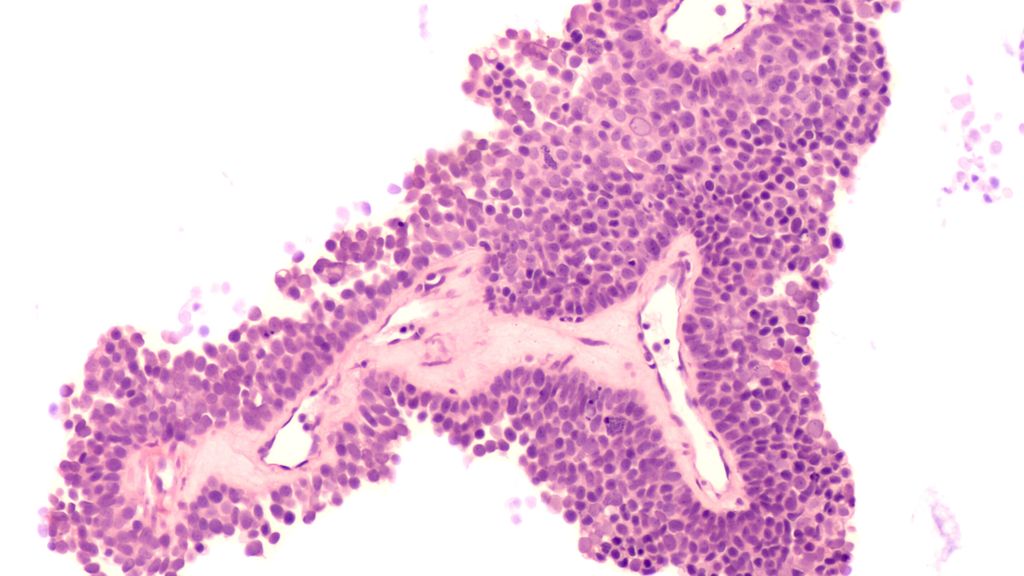

Dans le cas du carcinome pulmonaire non à petites cellules de stade IV sans mutations inductrices, des questions centrales se posent dans la pratique concernant la sélection du ...

Cette année encore, l’European Lung Cancer Congress (ELCC) a été l’occasion de présenter des approches thérapeutiques innovantes et prometteuses, comprenant à la fois des traitements ...

De nouvelles données d’études du Congrès Européen sur le Cancer du Poumon (ELCC) pourraient modifier durablement le paysage thérapeutique du carcinome pulmonaire non à petites cellules ( ...